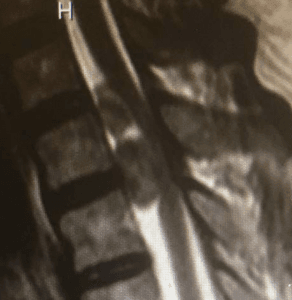

Tumor benigno intra raquídeo extradural e inestabilidad degenerativa asociada

Femenino, 55

Lumbocruralgia. Dolor lumbar axial, mecánico, progresivo e invalidante. Constante, en posición de pie y acostada, nocturno y diurno.